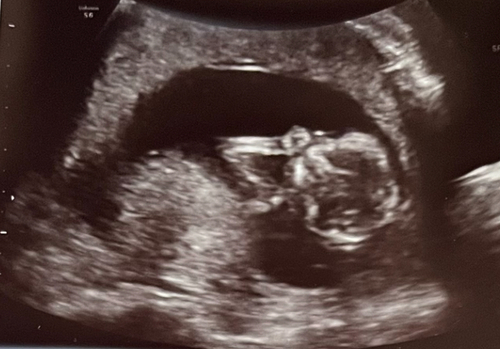

Das war das erste Ultraschallbild. Da war ich 9+5 nun sind wir schon bei 14+0😃 die Zeit vergeht so so schnell